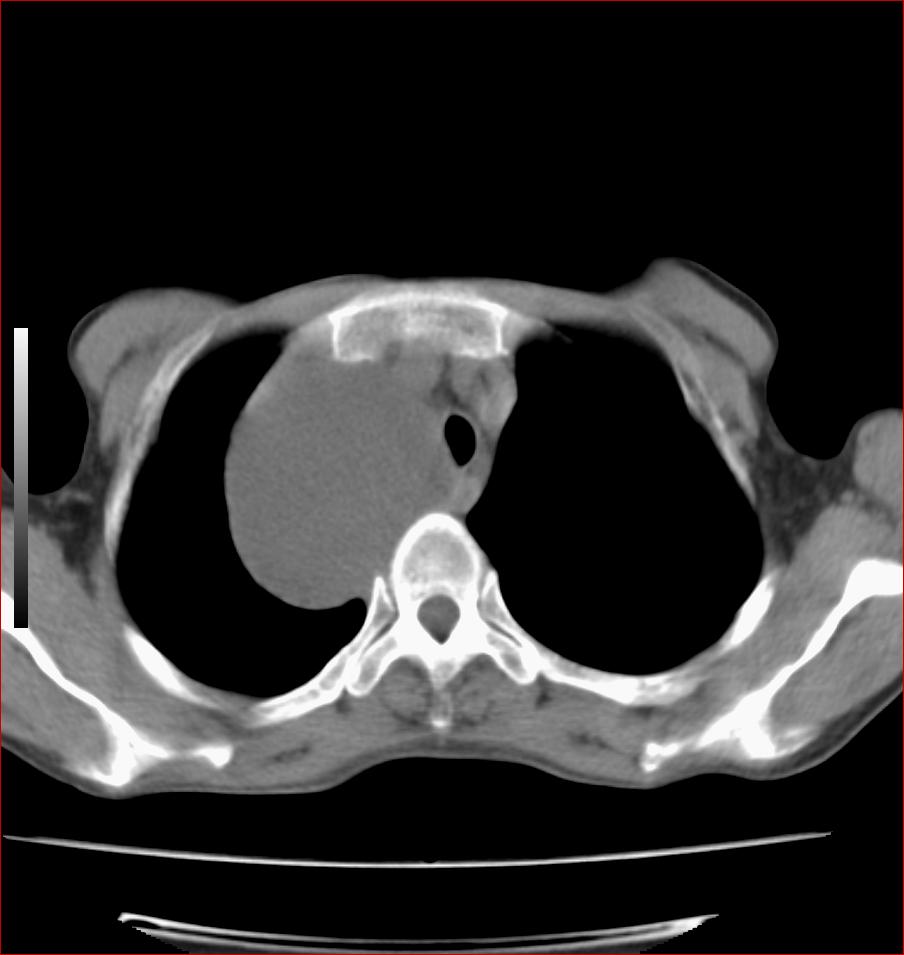

标题: CT17110:F56Y,纵隔囊肿;胸腺?淋巴?请各位老师看看 [打印本页]

女性患者 56 咽痛伴声嘶10+天入院。

右上纵隔囊性占位性病变;考虑支气管囊肿可能。

病变紧贴气管右壁,两者相互压迫,考虑支气管囊肿!

见相互挤压征,考虑气管囊肿,建议ct增强扫描

病变紧贴气管右壁,两者相互压迫,考虑支气管囊肿!  建议强化

纵隔前肠性囊性,支气管囊肿可能性大